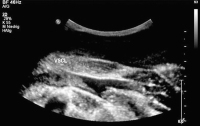

Thrombus - Vena subclavia

Abbildung 2: Thrombus in der Vena subclavia, Längsschnitt.